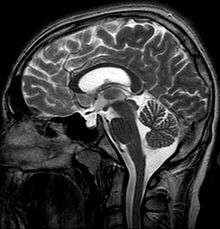

Empty sella syndrome (abbreviated ESS) is where the pituitary gland shrinks or becomes flattened,[1] filling the sella turcica, or "Turkish Saddle", with cerebrospinal fluid on imaging instead of the normal pituitary. ESS can be found in the radiological workup of pituitary disorders, or as an incidental finding when imaging the brain.

MRI scans are useful in evaluating ESS and differentiating it from other disorders that produce an enlarged sella.